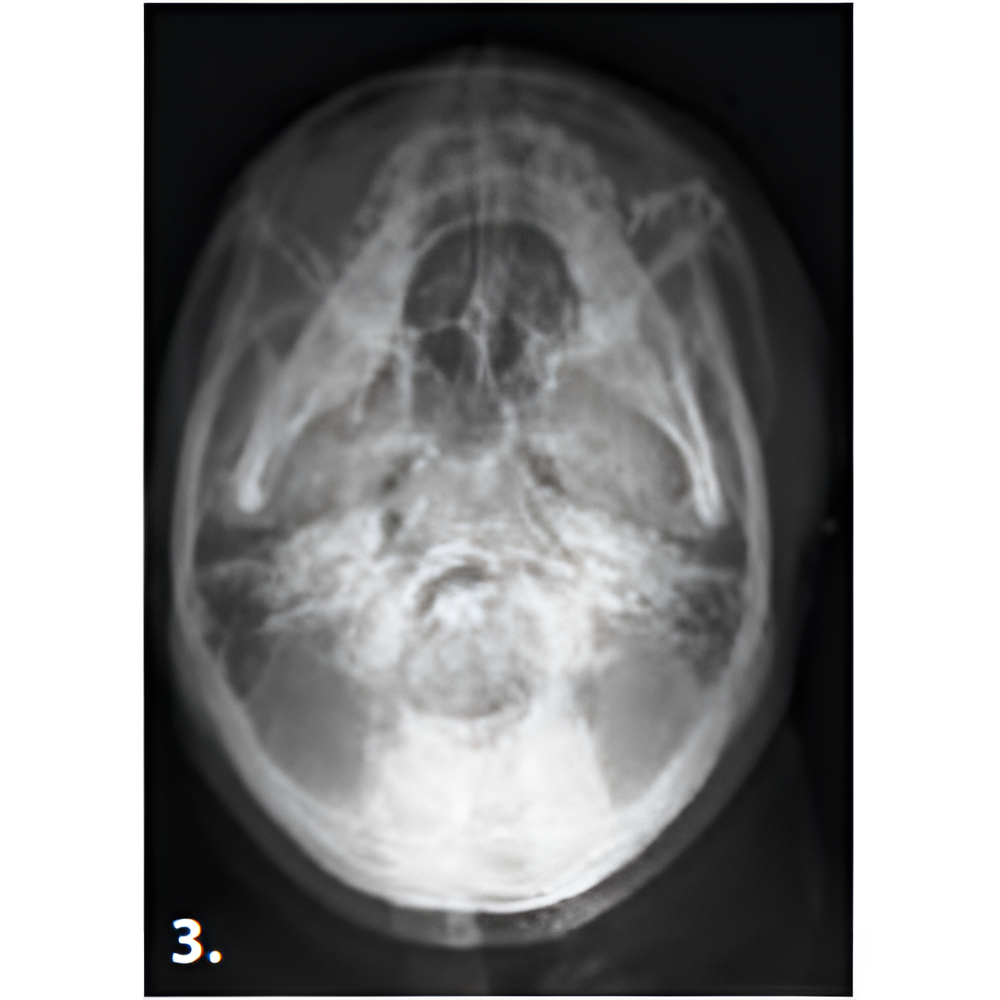

Hyperion X9 pro meets every diagnostic requirement by easily integrating into the work flow and guaranteeing maximum comfort for both patient and operator. SuperHD quality images that allow the doctor to make a correct diagnosis, thanks to easy and completely guided procedures. Full accessibility and user-friendliness with the innovative full-touch control panel and fast Face To Face positioning which guarantees maximum comfort to both patient and operator.

- Panoramic

- Cephalometric

- SuperHD CB3D

- 3D Images